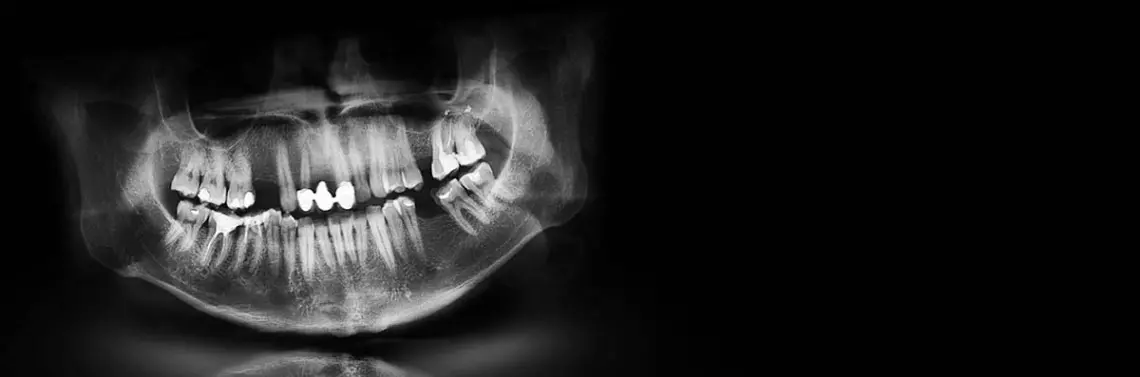

Badanie pantomograficzne jest standardowym przeglądowym badaniem potrzeb stomatologicznych pacjenta. Widać na nim właściwie cały obszar układu stomatognatycznego – wyrostki zębodołowe, tkanki szczęki i żuchwy, stawy skroniowo-żuchwowe, a także przednią ścianę zatok szczękowych. Dzięki temu możliwa jest diagnostyka pourazowa: złamania tkanek twardych – kości szczęki, żuchwy czy poszczególnych zębów, zmiany zapalne – torbiele, ziarniniaki, a także wszelkie anomalie rozwojowe.

Biorąc pod uwagę zakres badania i sposób prowadzenia wiązki promieniowania RTG, widoczne tu będą duże zmiany – badanie jest dość „zgrubne”, szczególnie jeśli chodzi o zmiany OKW czy pęknięcia. Mogą one zostać niezauważone w związku z nakładaniem się na siebie cieni poszczególnych struktur anatomicznych, a także rozdzielczością, którą takie badania się cechują.

W takich sytuacjach najczęściej posiłkujemy się dodatkowo dokładniejszymi badaniami wewnątrzustnymi. Oczywiście ich zakres jest dużo mniejszy (ograniczony powierzchnią aktywną czujnika wewnątrzustnego bądź rozmiarem płytki fosforowej). Ponadto nadal mówimy o badaniach dwuwymiarowych, czyli tu także cienie struktur nakładają się na siebie, utrudniając diagnostykę (zdj. 1).